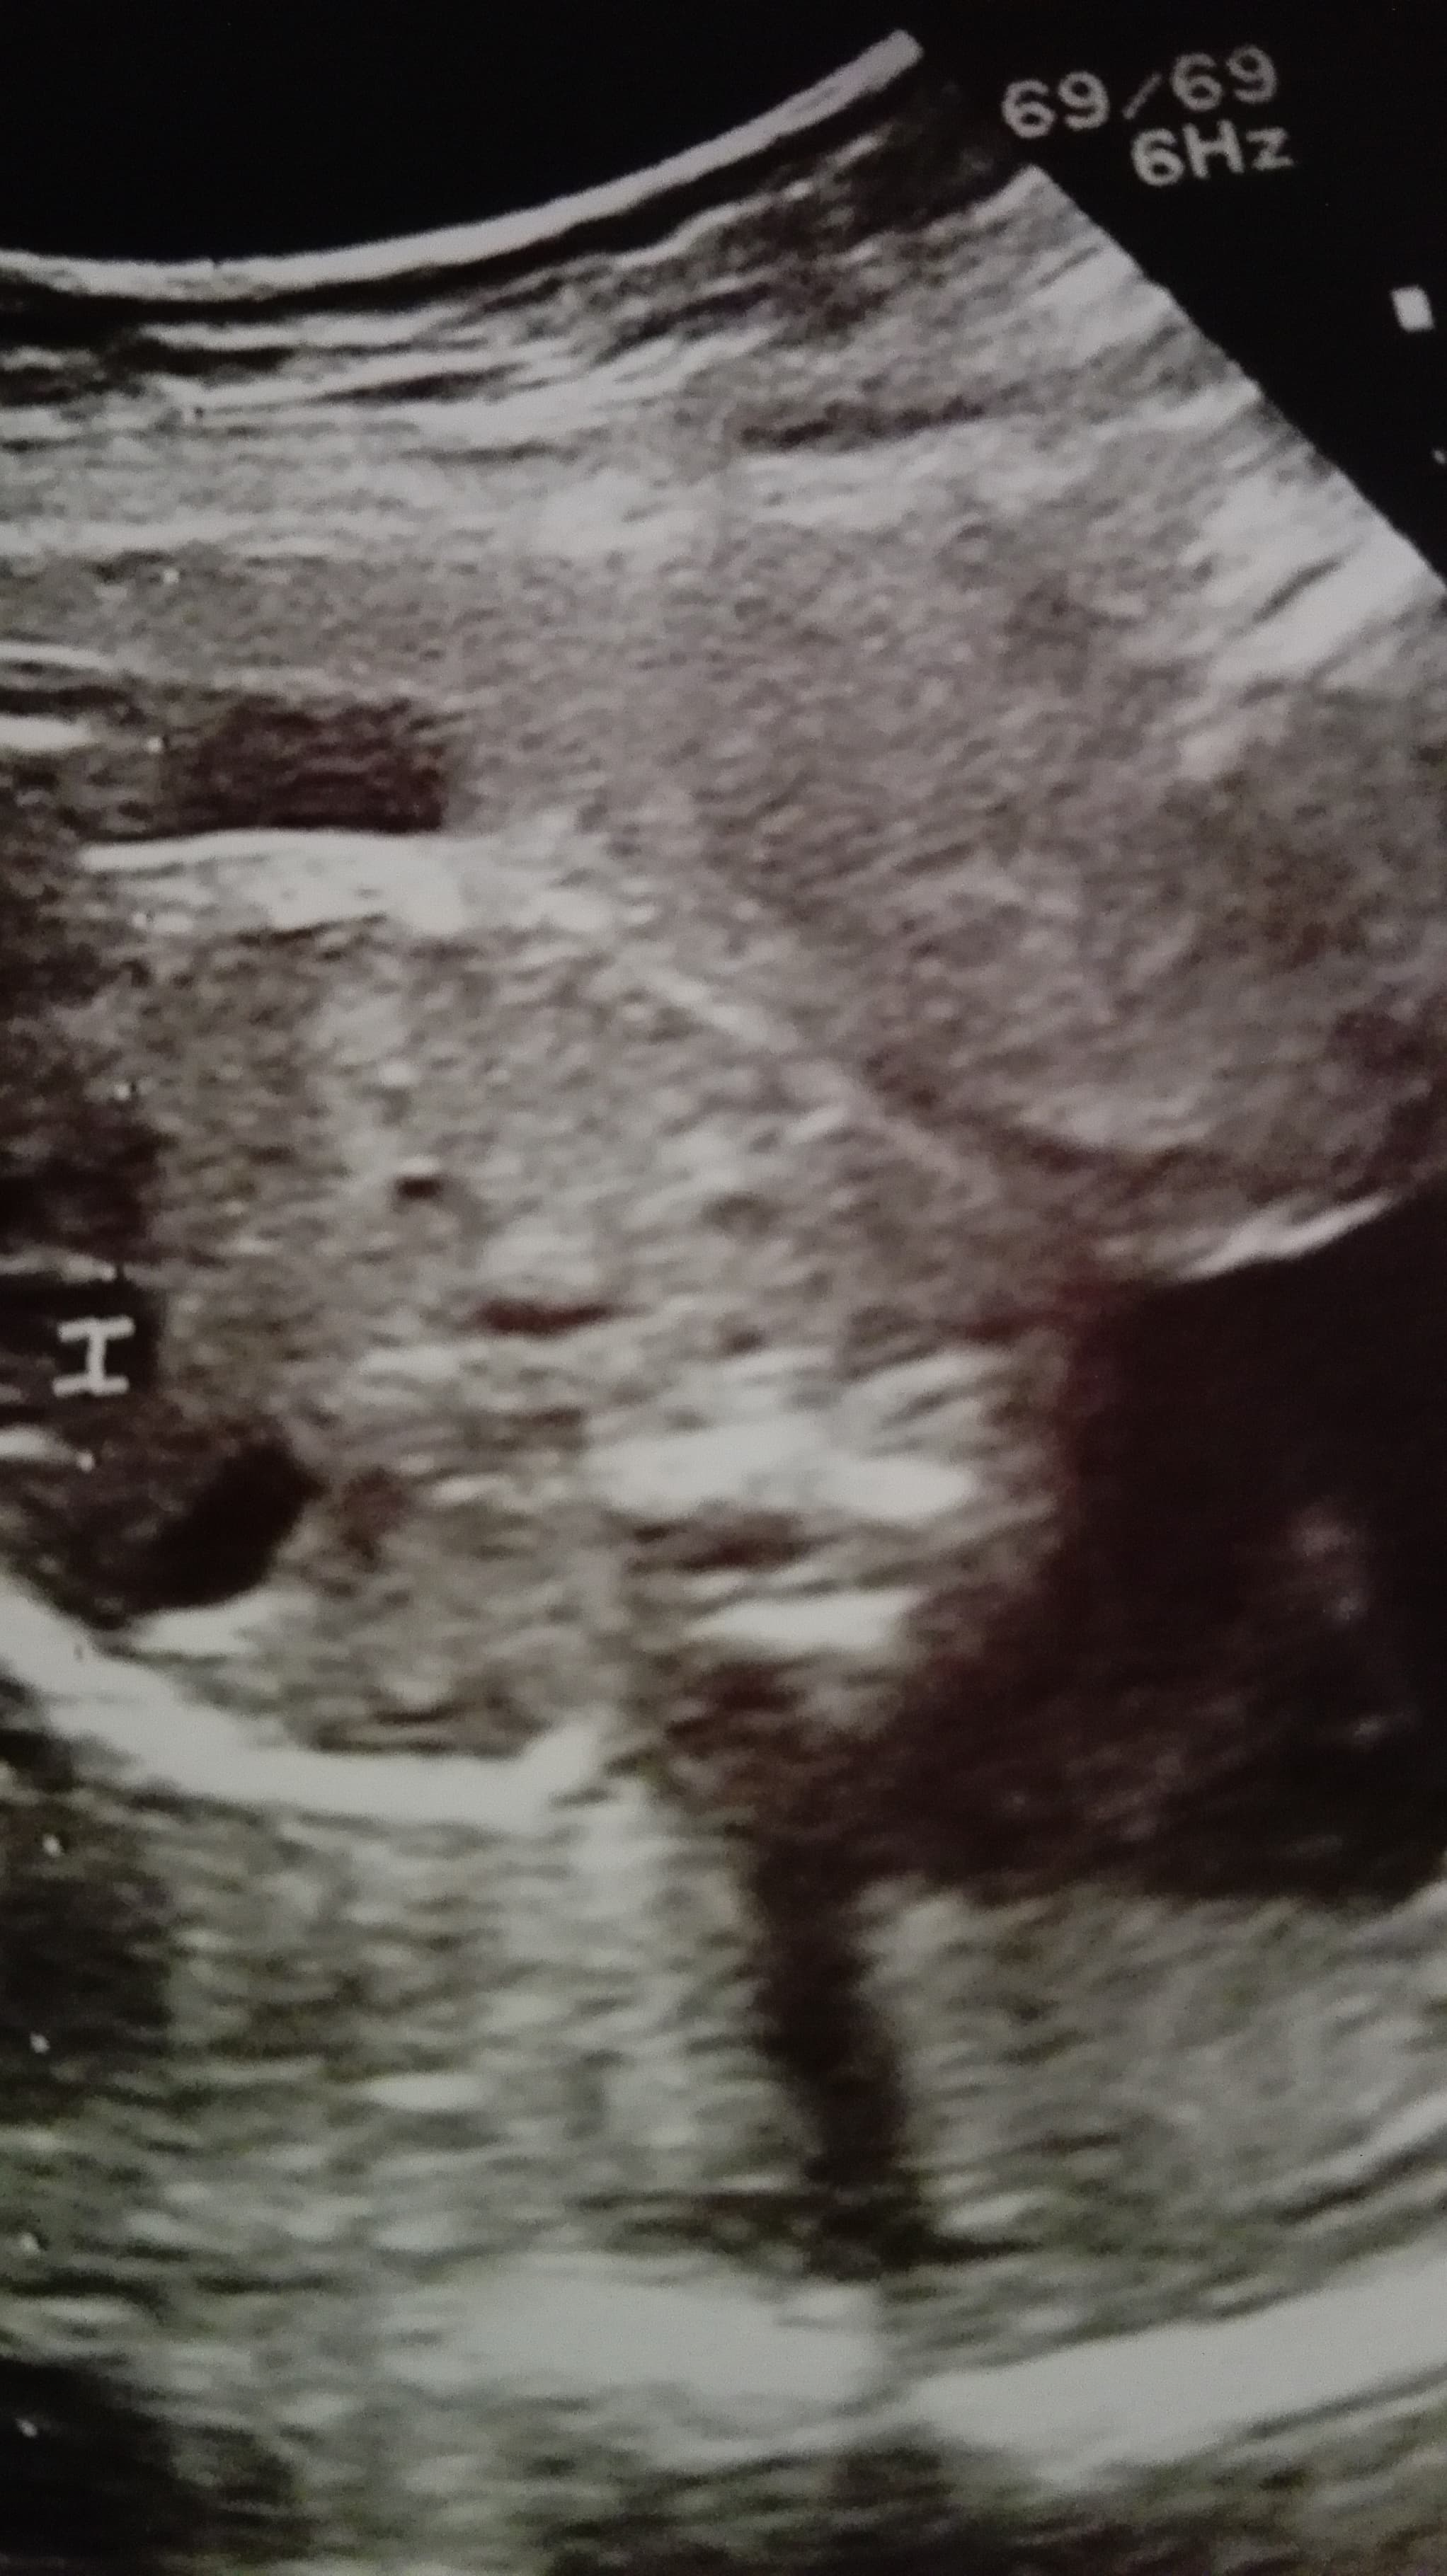

Kobietki, czy ja mam zwidy, czy tam widać twarzyczkę dziecka?

Załączniki

• Helka.jpg

Helka.jpg

408,4 KB · Wyświetleń: 107